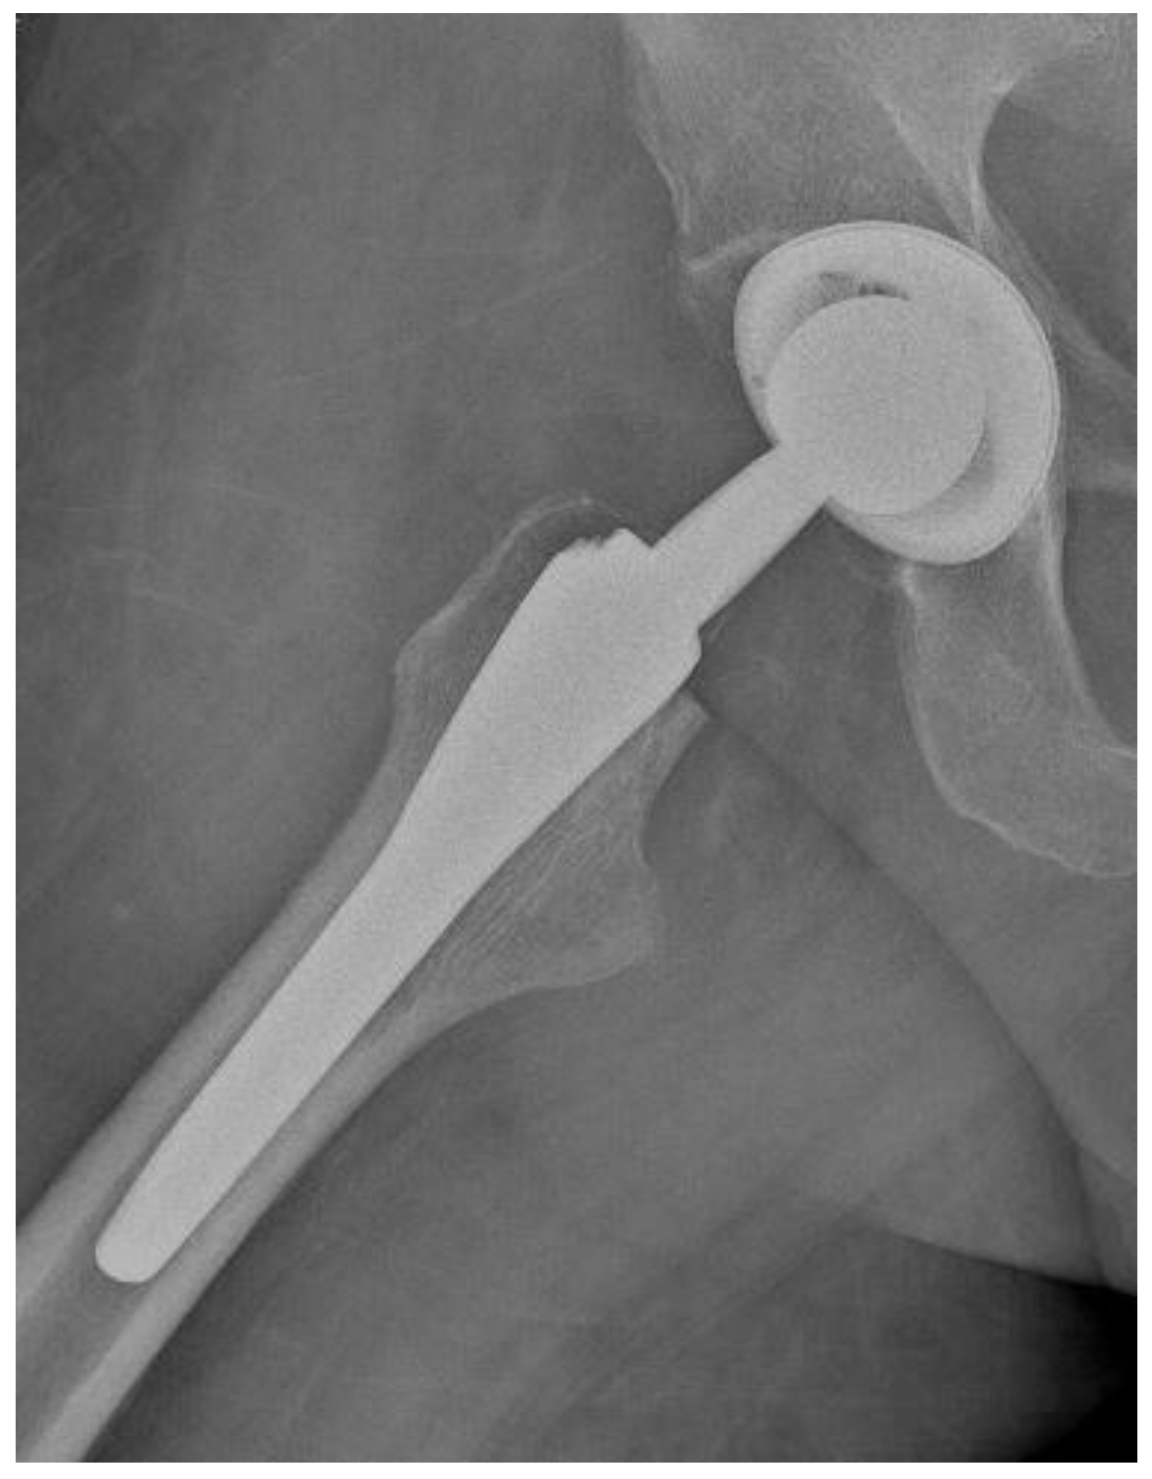

Of the 84 patients enrolled in this study, 44 patients (52.4%) received a THA with a straight stem (group A) (Figure 1 and Figure 2) and 40 patients (47.6%) received a THA with an anatomical stem (group B) (Figure 3 and Figure 4).

Figure 3.

Antero-posterior X-rays view of a total hip arthroplasty with anatomical stem (group B).

Figure 4.

Axial X-rays view of a total hip arthroplasty with anatomical stem (group B).